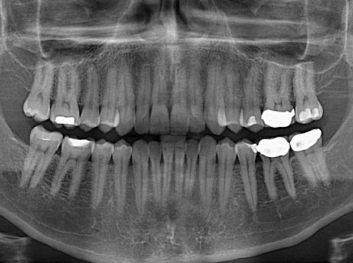

在體外測試中,材料刺激干細(xì)胞進(jìn)入牙本質(zhì)的增殖和分化速度,促進(jìn)形成牙齒骨組織。研究人員認(rèn)為,一旦材料在受損牙齒中應(yīng)用,這些干細(xì)胞可以自動修復(fù)來自填充物上的損壞。在本質(zhì)上,該生物材料將使牙齒自愈。

在未來,Adam Celiz說,可再生材料能制成各種填充物以便受損牙齒的自身治愈,降低補牙失敗率,甚至?xí)蟛糠秩藢Ω苤委煹男枰?/p>

這個研究團隊今年還榮獲英國皇家化學(xué)學(xué)會(Royal Society of Chemistry)新興技術(shù)獎材料類第二名。